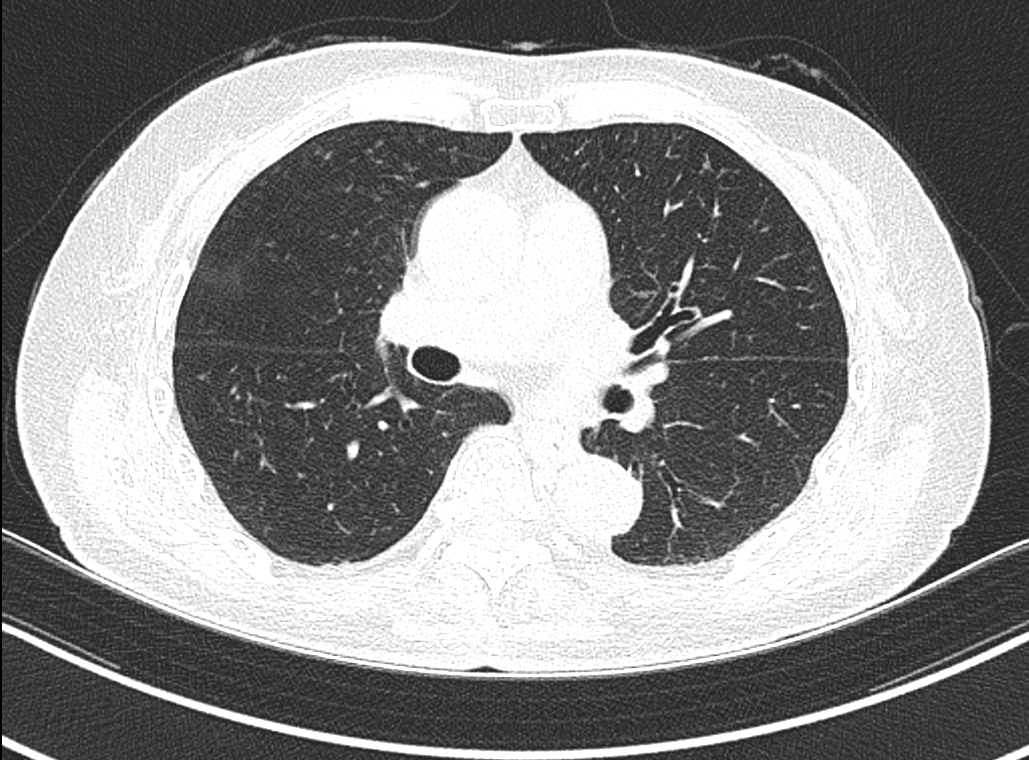

폐 CT(Computed Tomography)는 흉부를 X-ray로 여러 각도에서 촬영하고, 이를 컴퓨터로 재구성하여 폐 조직과 기관의 단면을 정밀하게 확인하는 영상검사입니다. 일반적인 흉부 X-ray보다 훨씬 더 높은 해상도를 제공해, 작은 결절이나 병변도 조기에 발견할 수 있습니다.

저선량 폐 CT(Low Dose Chest CT)는 방사선 노출을 최소화하면서 폐를 정밀하게 촬영할 수 있는 방법으로, 폐암 조기검진에 가장 널리 사용됩니다. 특히 흡연력이 있는 50세 이상 성인에게 추천되며, 국가암검진 항목에도 포함되어 있습니다.